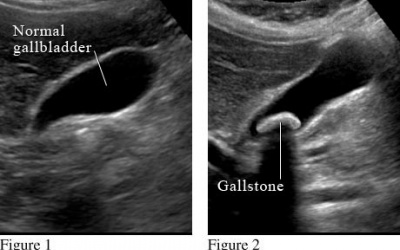

Sau khi cắt túi mật để chữa sỏi mật, tôi bị tiêu chảy nặng nhiều ngày nay. Tôi đã uống uống thuốc nhưng bệnh tiêu chảy vẫn không khỏi. Xin hỏi, có phải cắt túi mật khiến tôi bị...